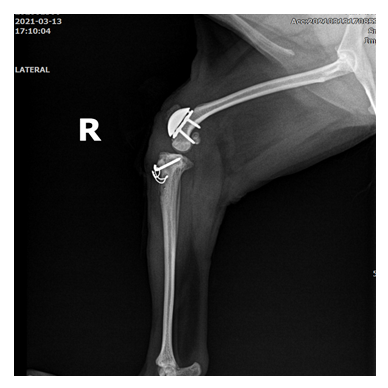

십자인대 파열 수술 전

십자인대 파열 수술 후